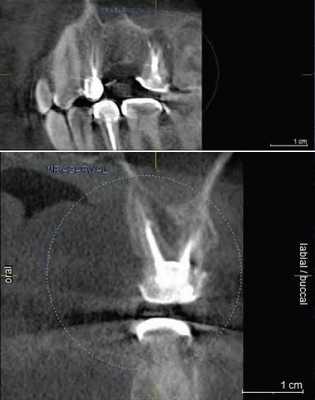

КЛКТ проводили на конусно-лучевом компьютерном томографе J. Morita Accuitomo 170, поле сканирования (FOV — field of view) — 8×8 см, угол ротации — 360, размер воксела (Voxel) — 0,16 мм.

С целью улучшения визуализации анатомических образований на компьютерном томографе при проведении сканирования применяли внутриротовой ретрактор соответствующего размера. Таким образом, отодвигая мягкие ткани губ и щек, исключали наслаивание теней и получали точную визуализацию анатомических образований пародонта.

— толщину десневого края (на рис. 3: Рис. 3. Сравнение исследуемых параметров. толщина десны);

— расстояние от десневого края до края наружной кортикальной пластинки (десневой край — альвеолярный гребень);

— расстояние от эмалево-цементной границы (ЭЦГ) до края наружной кортикальной пластинки (ЭЦГ — альвеолярный гребень).

Перед оценкой данных проводили настройку коррекции яркости и контрастности для максимальной визуализации вестибулярной костной пластинки, а также центрирование осей координат по вертикальной оси зуба для стандартизации прохождения среза.

Для повышения точности исследования проводили 3 вестибуло-оральных реформата относительно центральной оси с шагом 0,5 мм.

Толщина десны в исследуемой группе была меньше, чем в контрольной: соответственно 0,85 [0,7; 0,95] мм и 0,95 [0,8; 1] мм (см. рис. 3). В группах выявлены достоверные различия (p <0,05). Кроме того, толщина десневого края в обеих группах составляла менее 1 мм и по этому параметру можно считать десну «тонкой» (см. рис. 4). Рис. 4. Измерение толщины десны; использование ретрактора позволяет отодвинуть мягкие ткани губ от альвеолярного отростка.

Рис. 5. Измерение расстояния от ЭЦГ до альвеолярного гребня в области зуба 2.3 (без рецессии). В данном случае показатели на 3 реформатах составили: 2,72; 3,04; 3,20 мм.

Рис. 6. Измерение расстояния от ЭЦГ до альвеолярного гребня в области зуба 1.3 (клиническая рецессия — 1,6 мм). В данном случае показатели на 3 реформатах составили: 4,28; 4,48; 4,64 мм.